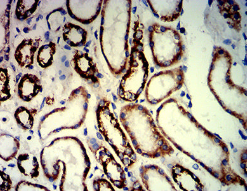

IHC    1/200-1/1000